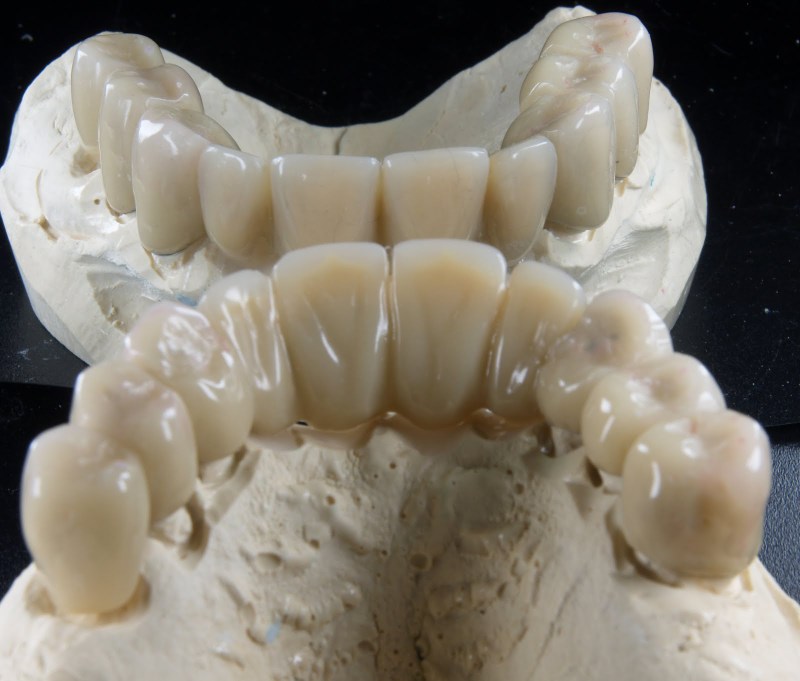

Meisterarbeit von Peter Dengel

Vom Langzeitprovisorium zur TEK 1 Arbeit